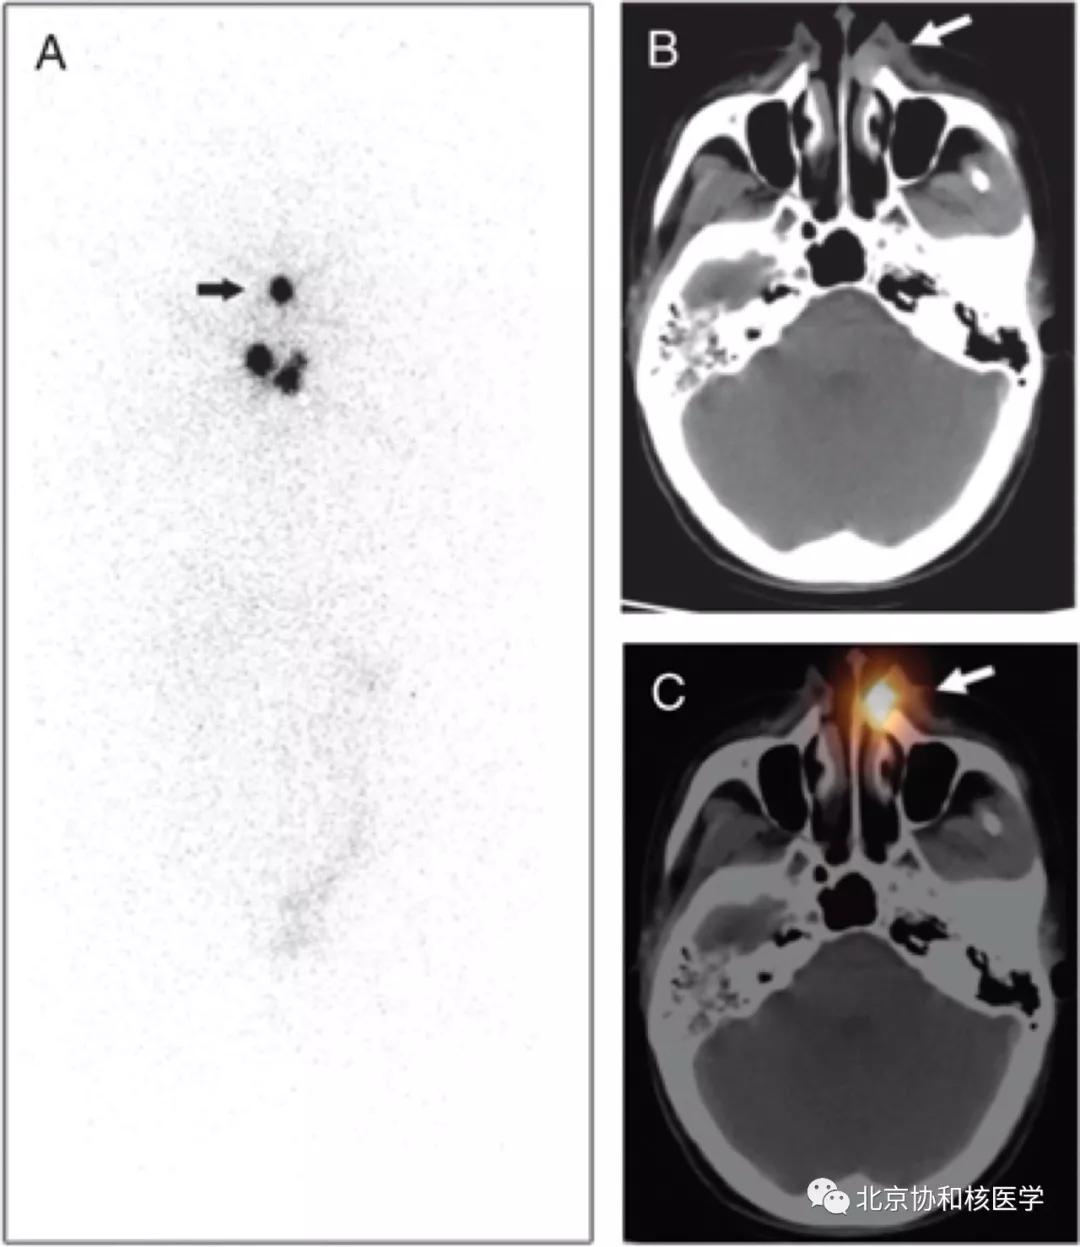

鼻腔息肉所致碘摄取,同时可见颈部残余甲状腺组织: